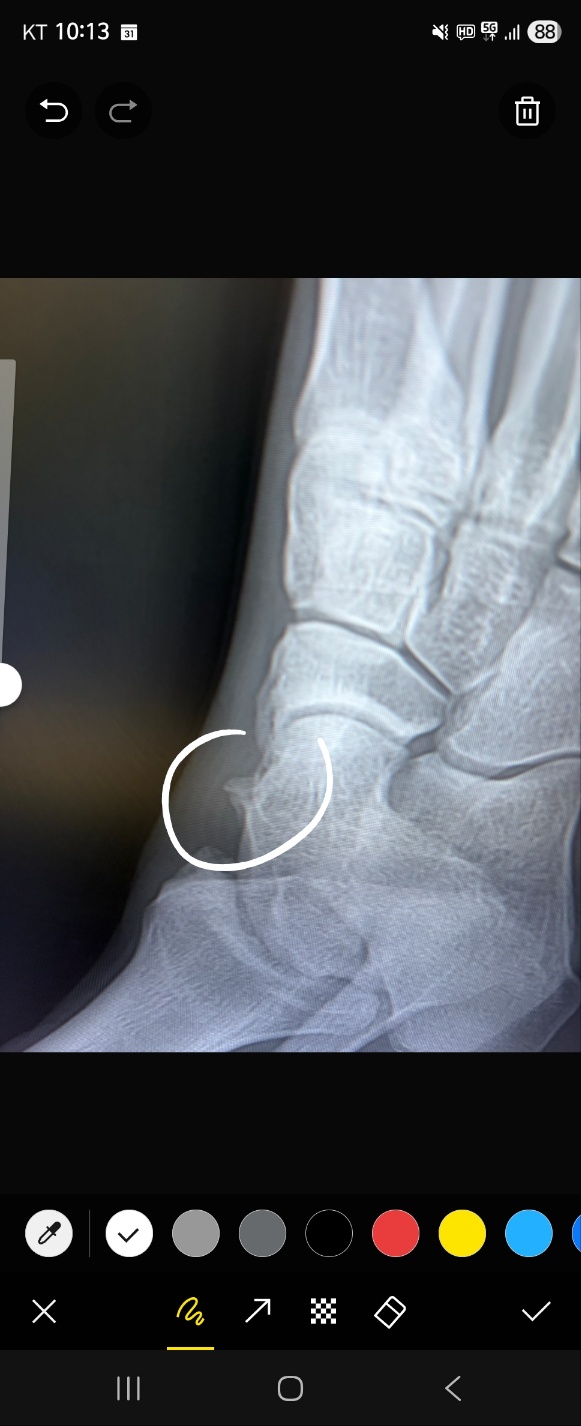

X-ray 사진(사진은 2년전쯤)을 첨부했는데, 어떤 증상인건지, 수술이 필요하다면

수술 및 입원 기간은 어떻게 되고 재활여부도 알려주시면 감사하겠습니다.

지금 올려주신 X레이 검사 사진과 동일하다면

부주상골 증후군으로 예상됩니다.